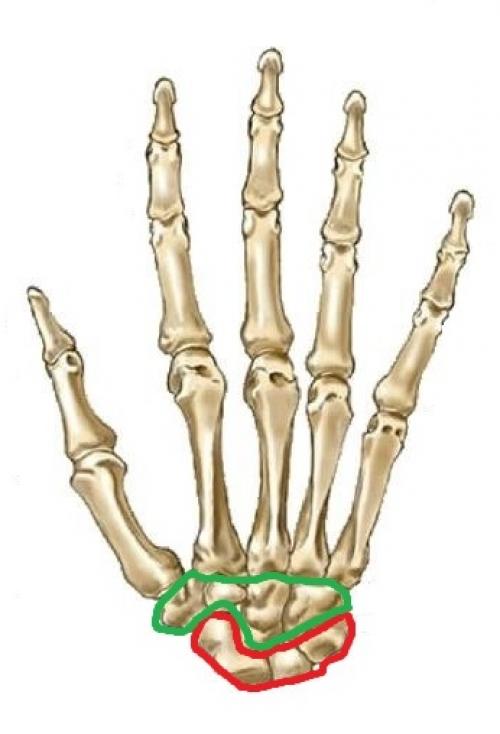

На этом рисунке я я выделил красным цветом проксимальный ряд костей запястья, а зелёным — дистальный.

А теперь давайте сориентируемся на настоящем рентгеновском снимке и попробуем на нём найти проксимальный и дистальный ряды костей запястья (цвета такие же):